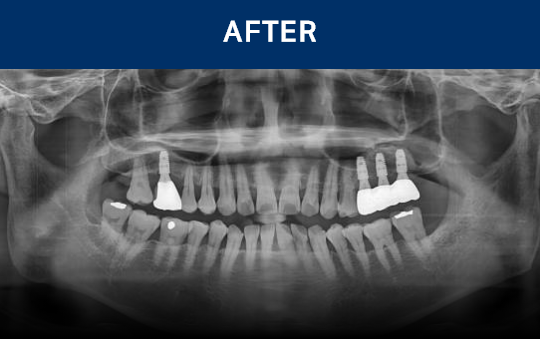

清晰可见的成果,

就是新吉种植牙

科值得信赖的证明.

通过种植牙, 让您无忧进食, 自在微笑, 重拾生活的舒适感